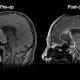

A 74-year-old man hospitalized with pneumonia was found to be hyponatremic with low cortisol levels. An MRI scan revealed a 4.8-centimeter giant pituitary adenoma. The patient had a history of blindness in the right eye and was experiencing progressive vision loss in the left eye with central 20/100 acuity. The patient’s hormonal workup showed panhypopituitarism and he was started on cortisol replacement therapy.

The patient was referred to the California Center for Pituitary Disorders at UCSF, where a specialized neurosurgery and neuroendocrine consultation led to the decision to move forward with surgery. An endoscopic endonasal approach was undertaken by neurosurgeon Manish Aghi, MD, PhD, and otolaryngologist Ivan El-Sayed, MD. Using 30-degree angled endoscopes, they were able to visualize the anterior extent of the tumor.

While the tumor extended anteriorly from the sellar/suprasellar space into the frontal lobe, it did not grow along the bony tuberculum and planum of the anterior skull base. Instead, there was a cuff of frontal lobe below the anterior extent of the tumor. Aghi used the angled endoscope to clean out all the anterior tumor, working at a 30-degree angle without causing any trauma to the frontal lobe underneath the tumor.

The patient was hospitalized for three days. Since the surgery, he has been taking levothyroxine to combat fatigue. The patient’s vision is slightly improved from its preoperative state and his energy is expected to improve over the next few months as the empty resection cavity collapses over time, further decompressing the frontal lobes.